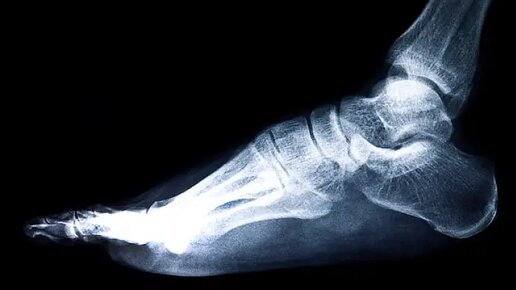

Лодыжка – это одна из наиболее уязвимых частей тела, которая часто подвергается травмам, особенно во время занятий спортом или в результате неудачных падений. Многие из нас сталкивались с ситуацией, когда после удара или неправильного движения возникает боль в лодыжке. Но как определить, это всего лишь растяжение или перелом? В этой статье разберемся, как распознать симптомы перелома, когда обращаться к врачу и какие методы диагностики помогут подтвердить травму. Перелом лодыжки – это серьёзное повреждение, и распознать его можно по ряду характерных признаков...